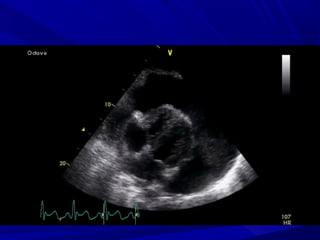

EchocardiographyEchocardiography

Normal in acute pericarditisNormal in acute pericarditis

Pericardial fluidPericardial fluid

Pericardial thicknessPericardial thickness

> 20 ml posteriorly> 20 ml posteriorly

>200ml anteriorly and posteriorly>200ml anteriorly and posteriorly

Mild < 5 mm in diastole (50-100ml)Mild < 5 mm in diastole (50-100ml)

Moderate 5-20 mm (100-500 ml)Moderate 5-20 mm (100-500 ml)

Severe >20 mm (>500ml)Severe >20 mm (>500ml)